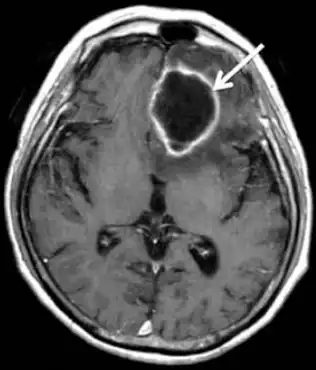

| MRI of brain revealed a mass in left frontal lobe that was ring-enhanced | |